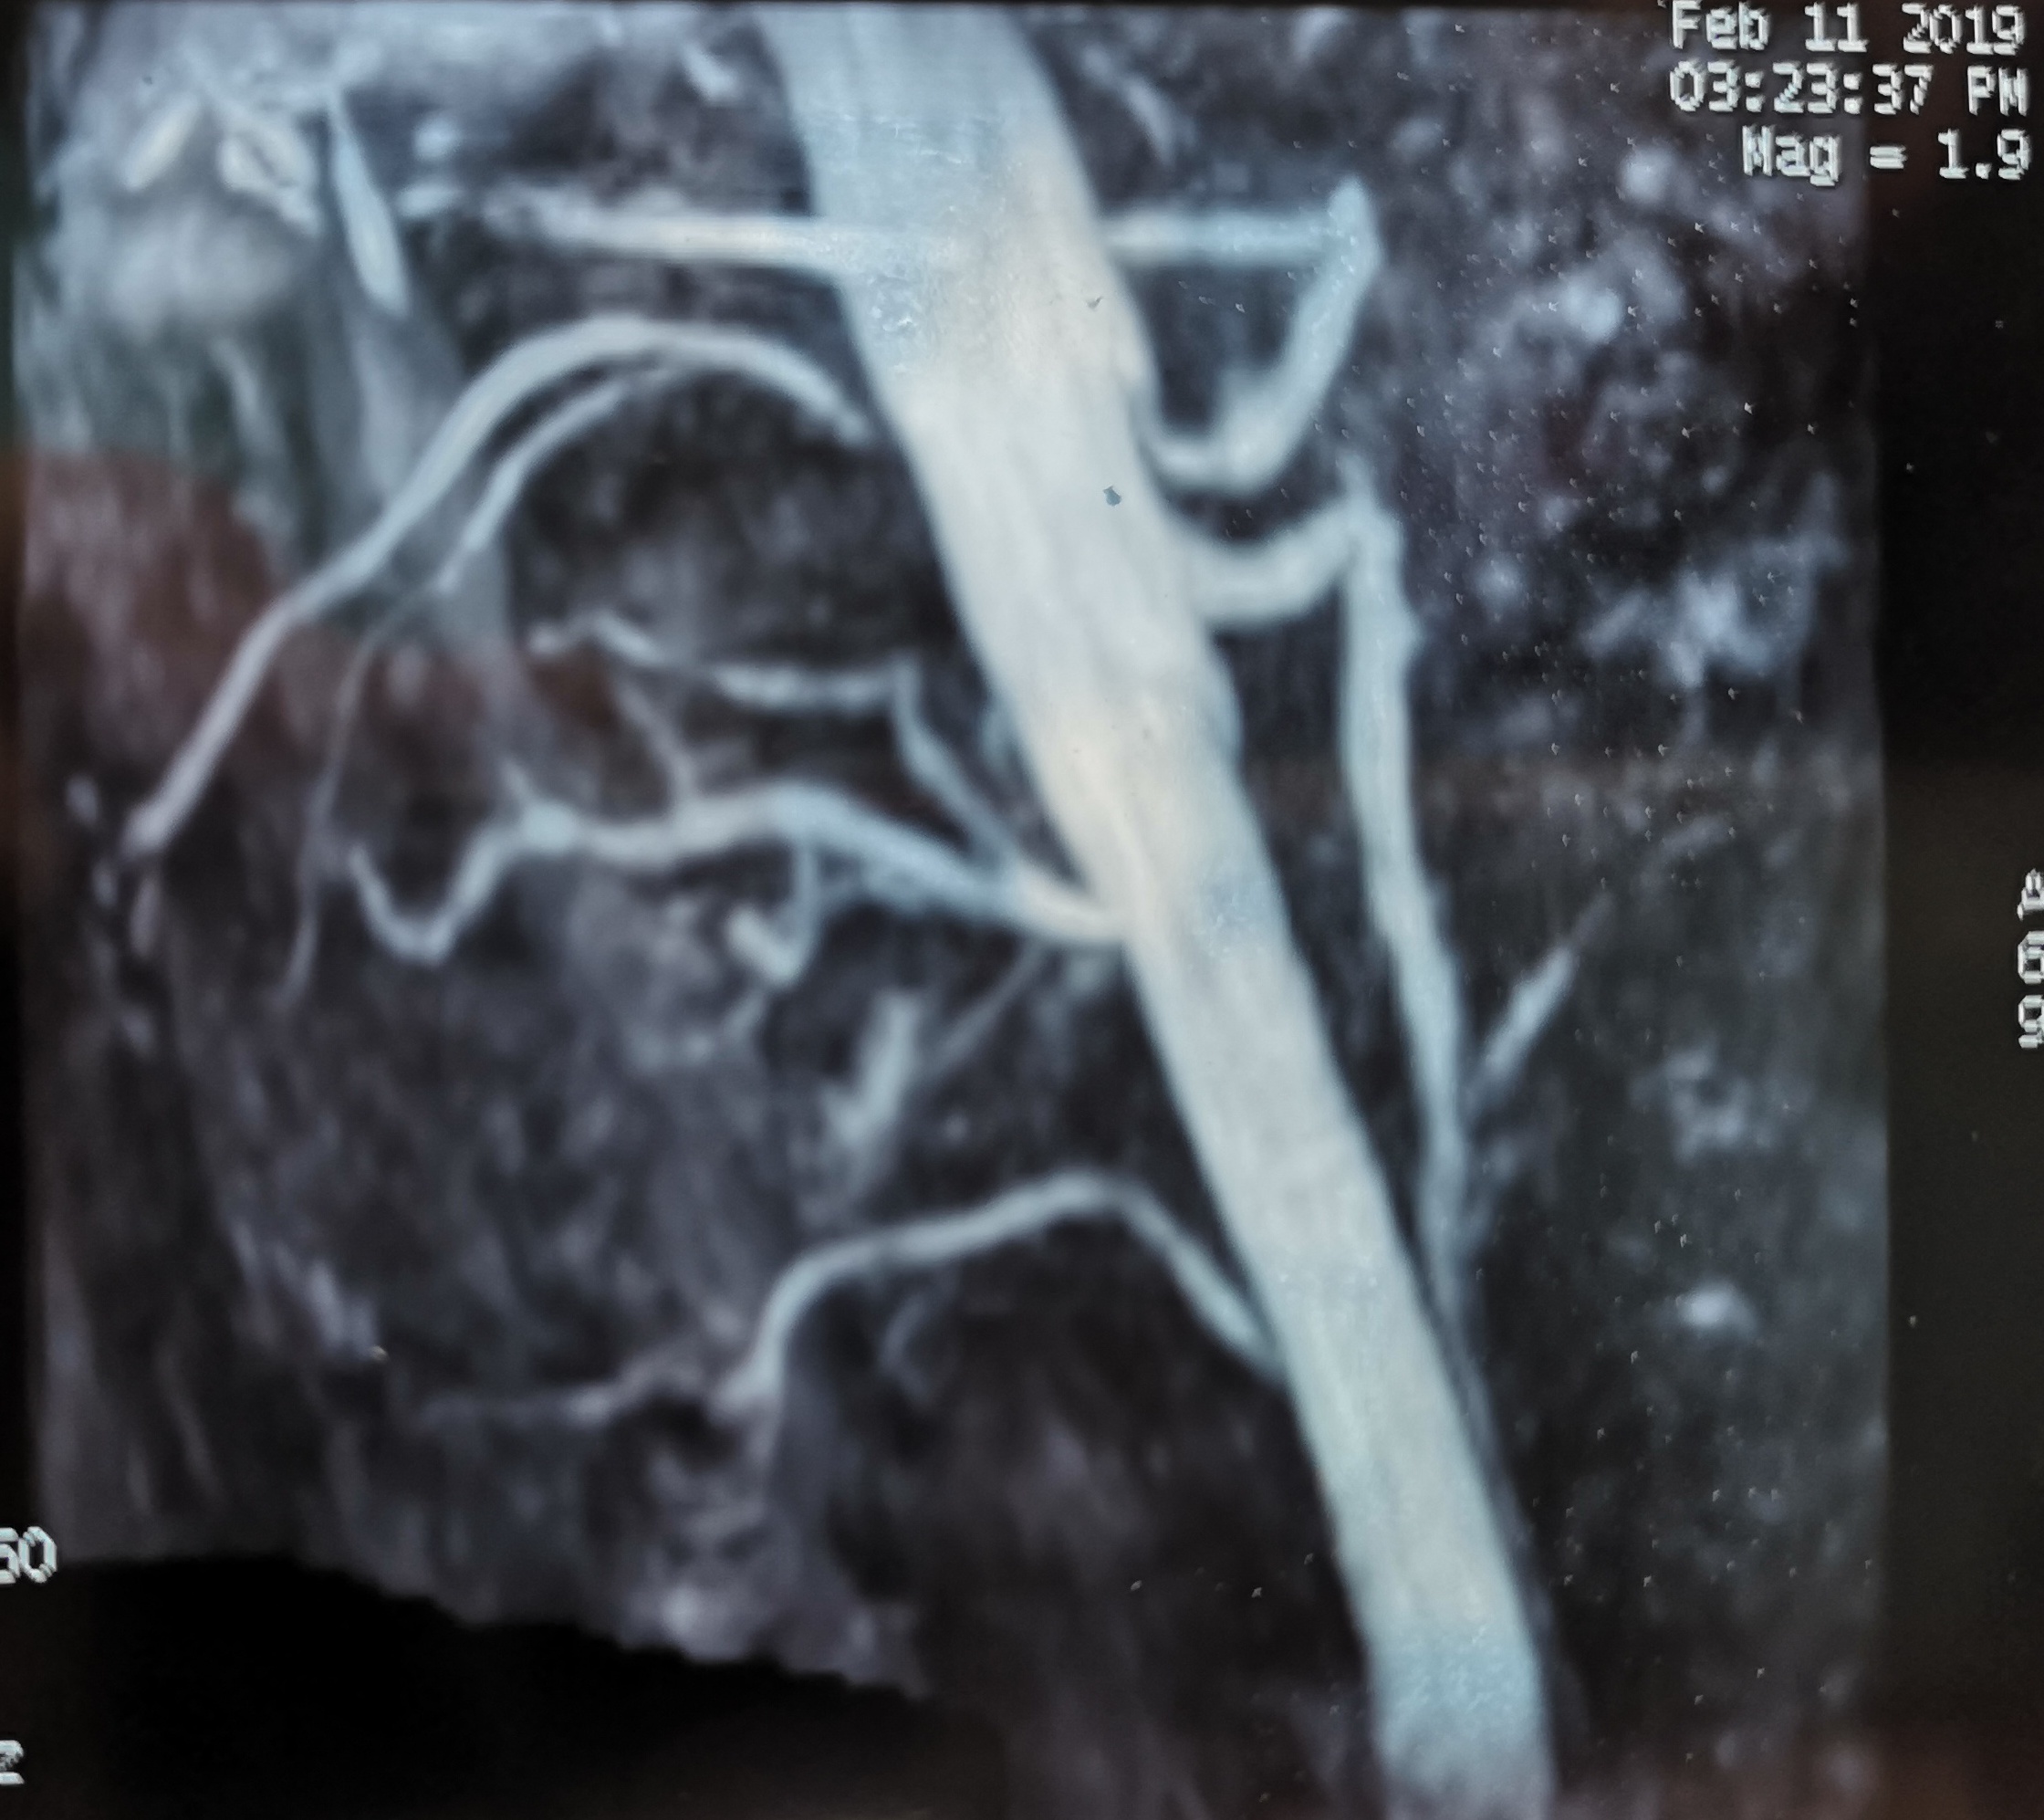

我一看片子,发现这病我认识!该患者的影像有特点,患者右肾动脉开口有狭窄,肠系膜上动脉不窄,但扭曲,腹腔干起始后有明显的向下弯曲,呈“V”字形(图1),下行段有狭窄。看来这是患者症状的罪魁祸首。这种患者不吃饭时没任何不适,一旦吃饭,胃肠道需要的血流量增大,但由于腹腔干狭窄,导致上消化道供血不足,出现类似下肢间歇性跛行的症状,就是腹痛,待胃肠道逐渐排空后,症状缓解,由此患者会出现进食相关腹痛,影响进食,导致患者不敢进食,出现消瘦。

图1. 右肾动脉开口狭窄,肠系膜上动脉扭曲,腹腔干呈“V”字形